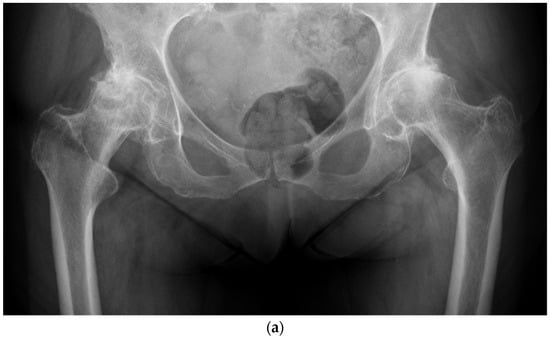

This paper will discuss the advantages of a large diameter head (LDH) THA. An LDH bearing is defined as a femoral head >36 mm and/or a cup-head diameters difference of 12 mm, i.e., 46 mm cup with a 36 mm head (Figure 1). LDH THA and hip resurfacing became widely accepted in the 1990s. The popular bearing at the time was Metal on Metal (MoM). This bearing delivered a solution to the problem of early wear and failure of metal-polyethylene (MoP) bearings in younger, more active individuals. The LDH also provided superior functional ability and stability compared to their conventional standard diameter head THAs. As complications associated with MoM began to rise, other bearing options, such as Ceramic on Ceramic (CoC), for LDH became more popular.

Figure 1.

(a) Anteroposterior pelvis radiograph of 19-year-old men with right femoral head avascular necrosis following a slipped capital femoral epiphysis treated with canulated screws. During preoperative templating, acetabular, and femoral components sizes were estimated to be small. (b) Preoperative lateral view of the right hip. (c) Postoperative anteroposterior pelvis radiograph showing a CoC LDH THA with a 13 mm conical stem and a 46 mm monobloc ceramic acetabular component with a bearing diameter of 36 mm. (d) Postoperative lateral view of the right hip replacement.